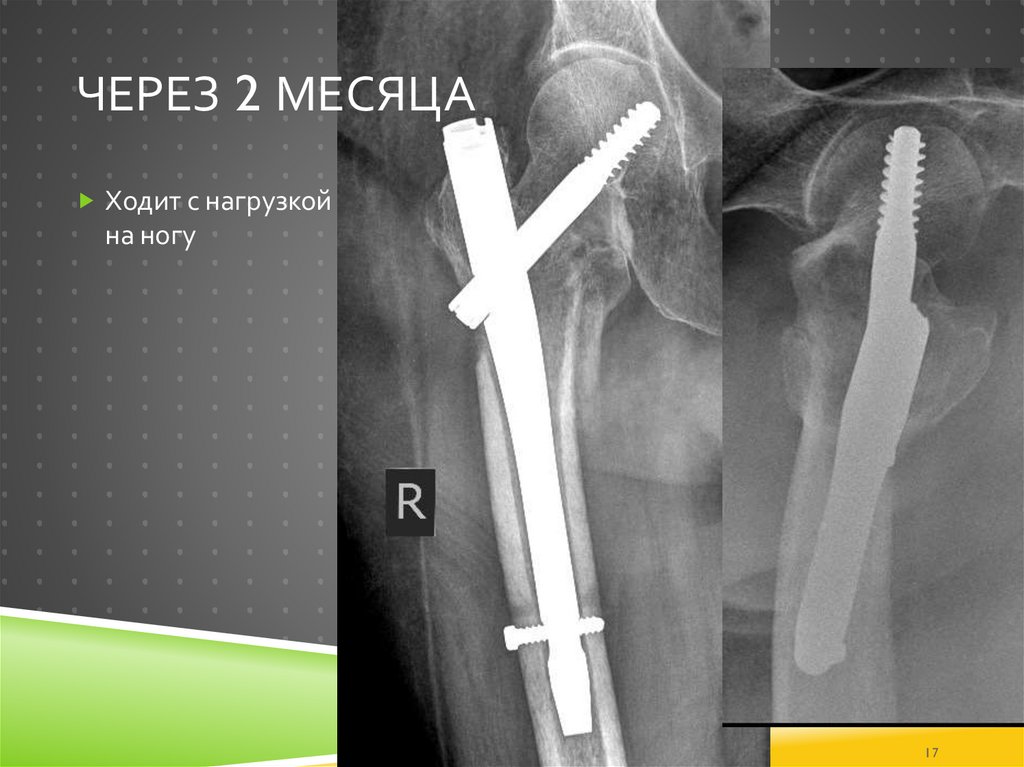

17. Через 2 месяца

ЧЕРЕЗ 2 МЕСЯЦА

Ходит с нагрузкой

на ногу